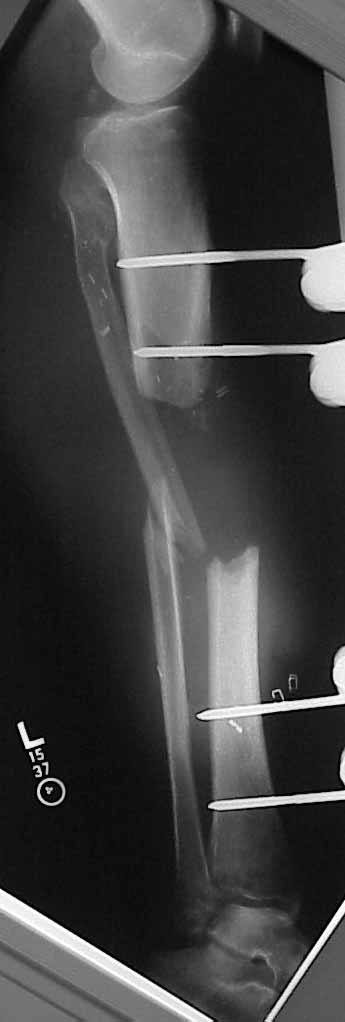

45 year old healthy non-smoker is six weeks post type 3B open tibial fracture. Latissimus flap looks perfect. Tibia is about 20 degrees externally rotated and in valgus. Intact pulses and sensation. Defect is 10-11 cm.

I'd love to nail and graft this one, rather than starting a 9 month Ilizarov lengthening.

Is it too big to nail and graft?

Does this require a bifocal lengthening?